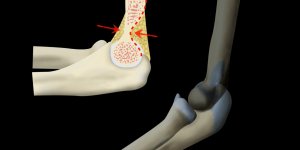

Supracondylar Fracture | X-ray

Simple x-ray interpretation of a supracondylar fracture and its mechanism of injury.